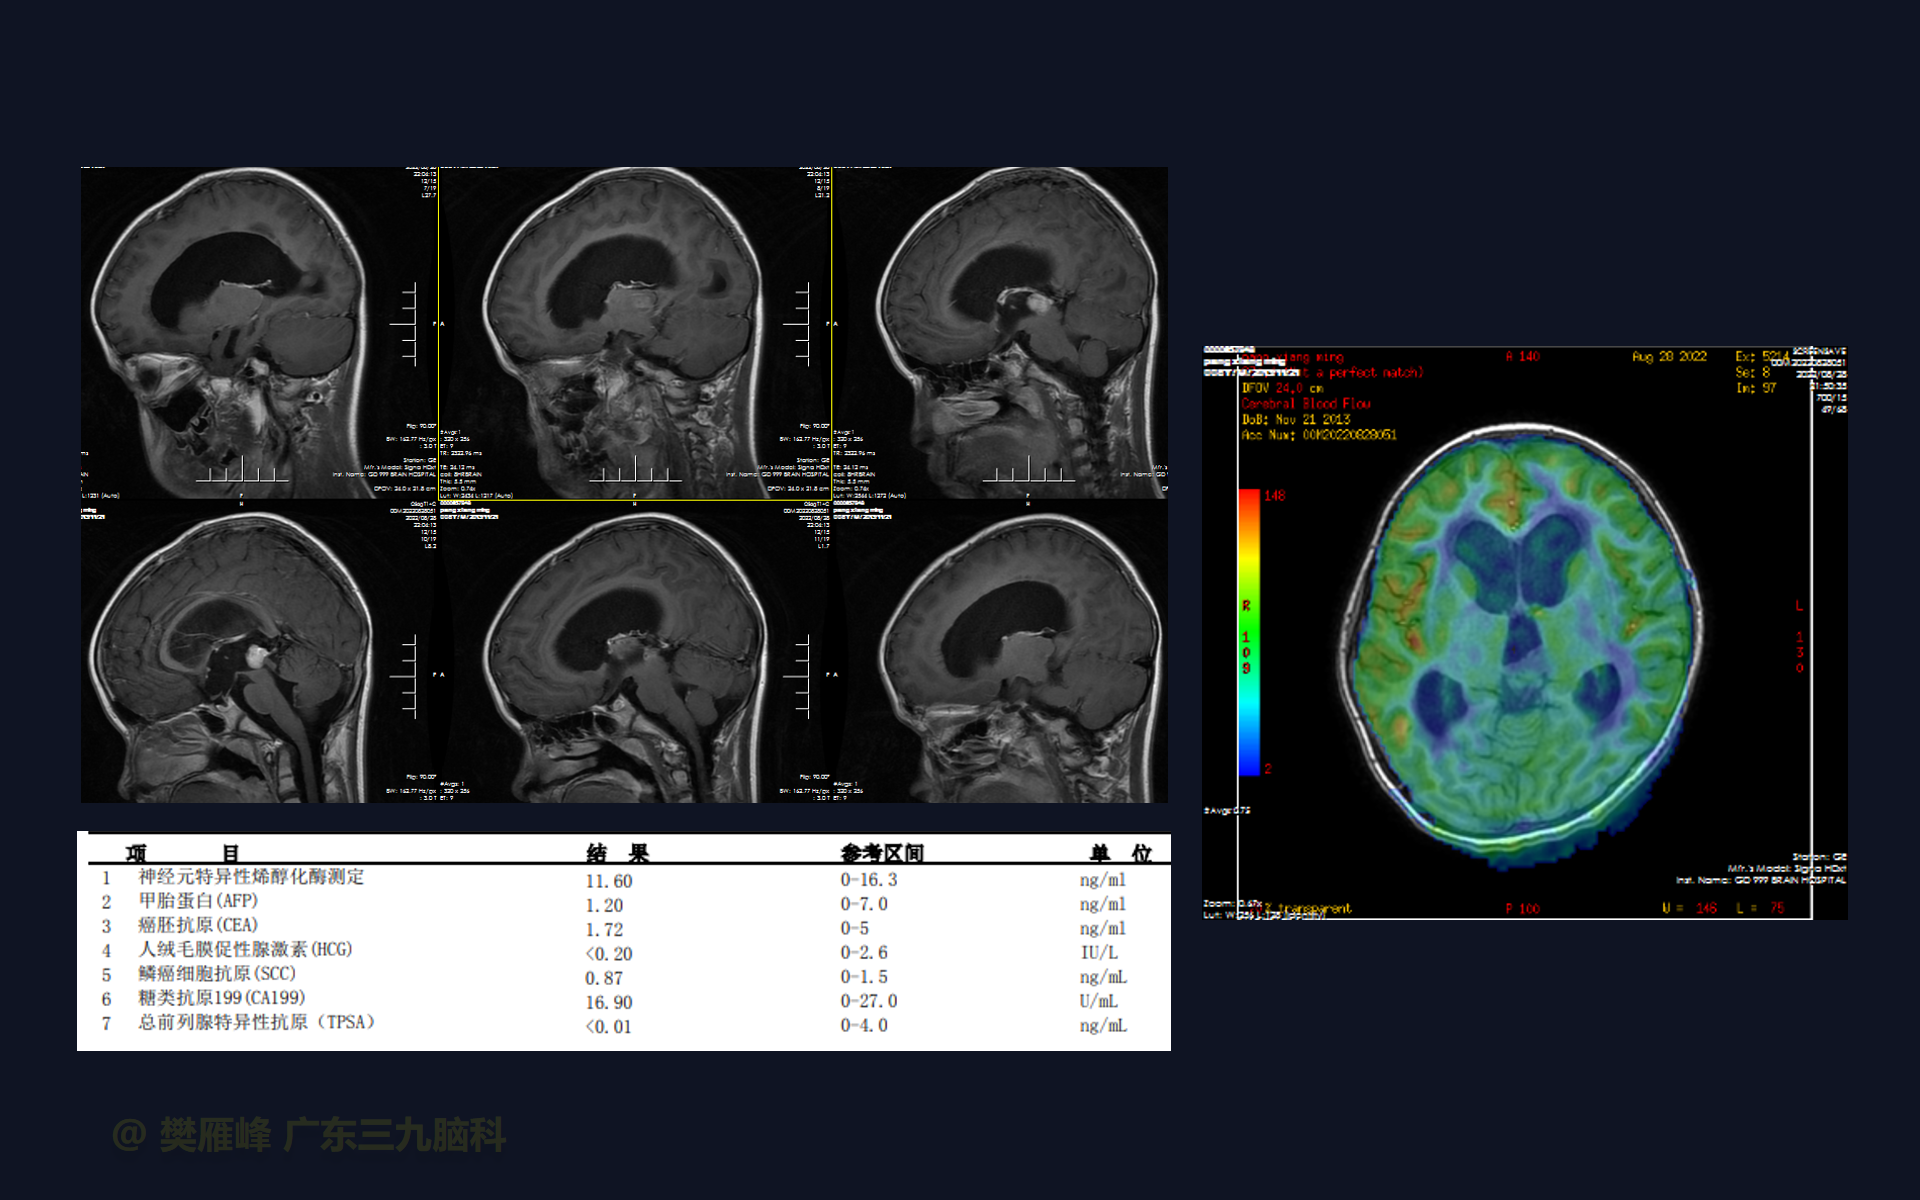

在这个二维手术视频中,展示了2例神经内镜下三脑室底造瘘+活检治疗三脑室后部肿瘤的方法。患者均为三脑室后部病变导致的梗阻性脑积水,病理结果1例为生殖细胞瘤,1例为淋巴瘤,在经过术后的放化疗病情均得到控制,生活质量满意。我们展示了安全的病变活检和第三脑室造瘘的技术要点,以最大限度减少术后继发脑积水和早期并发症。